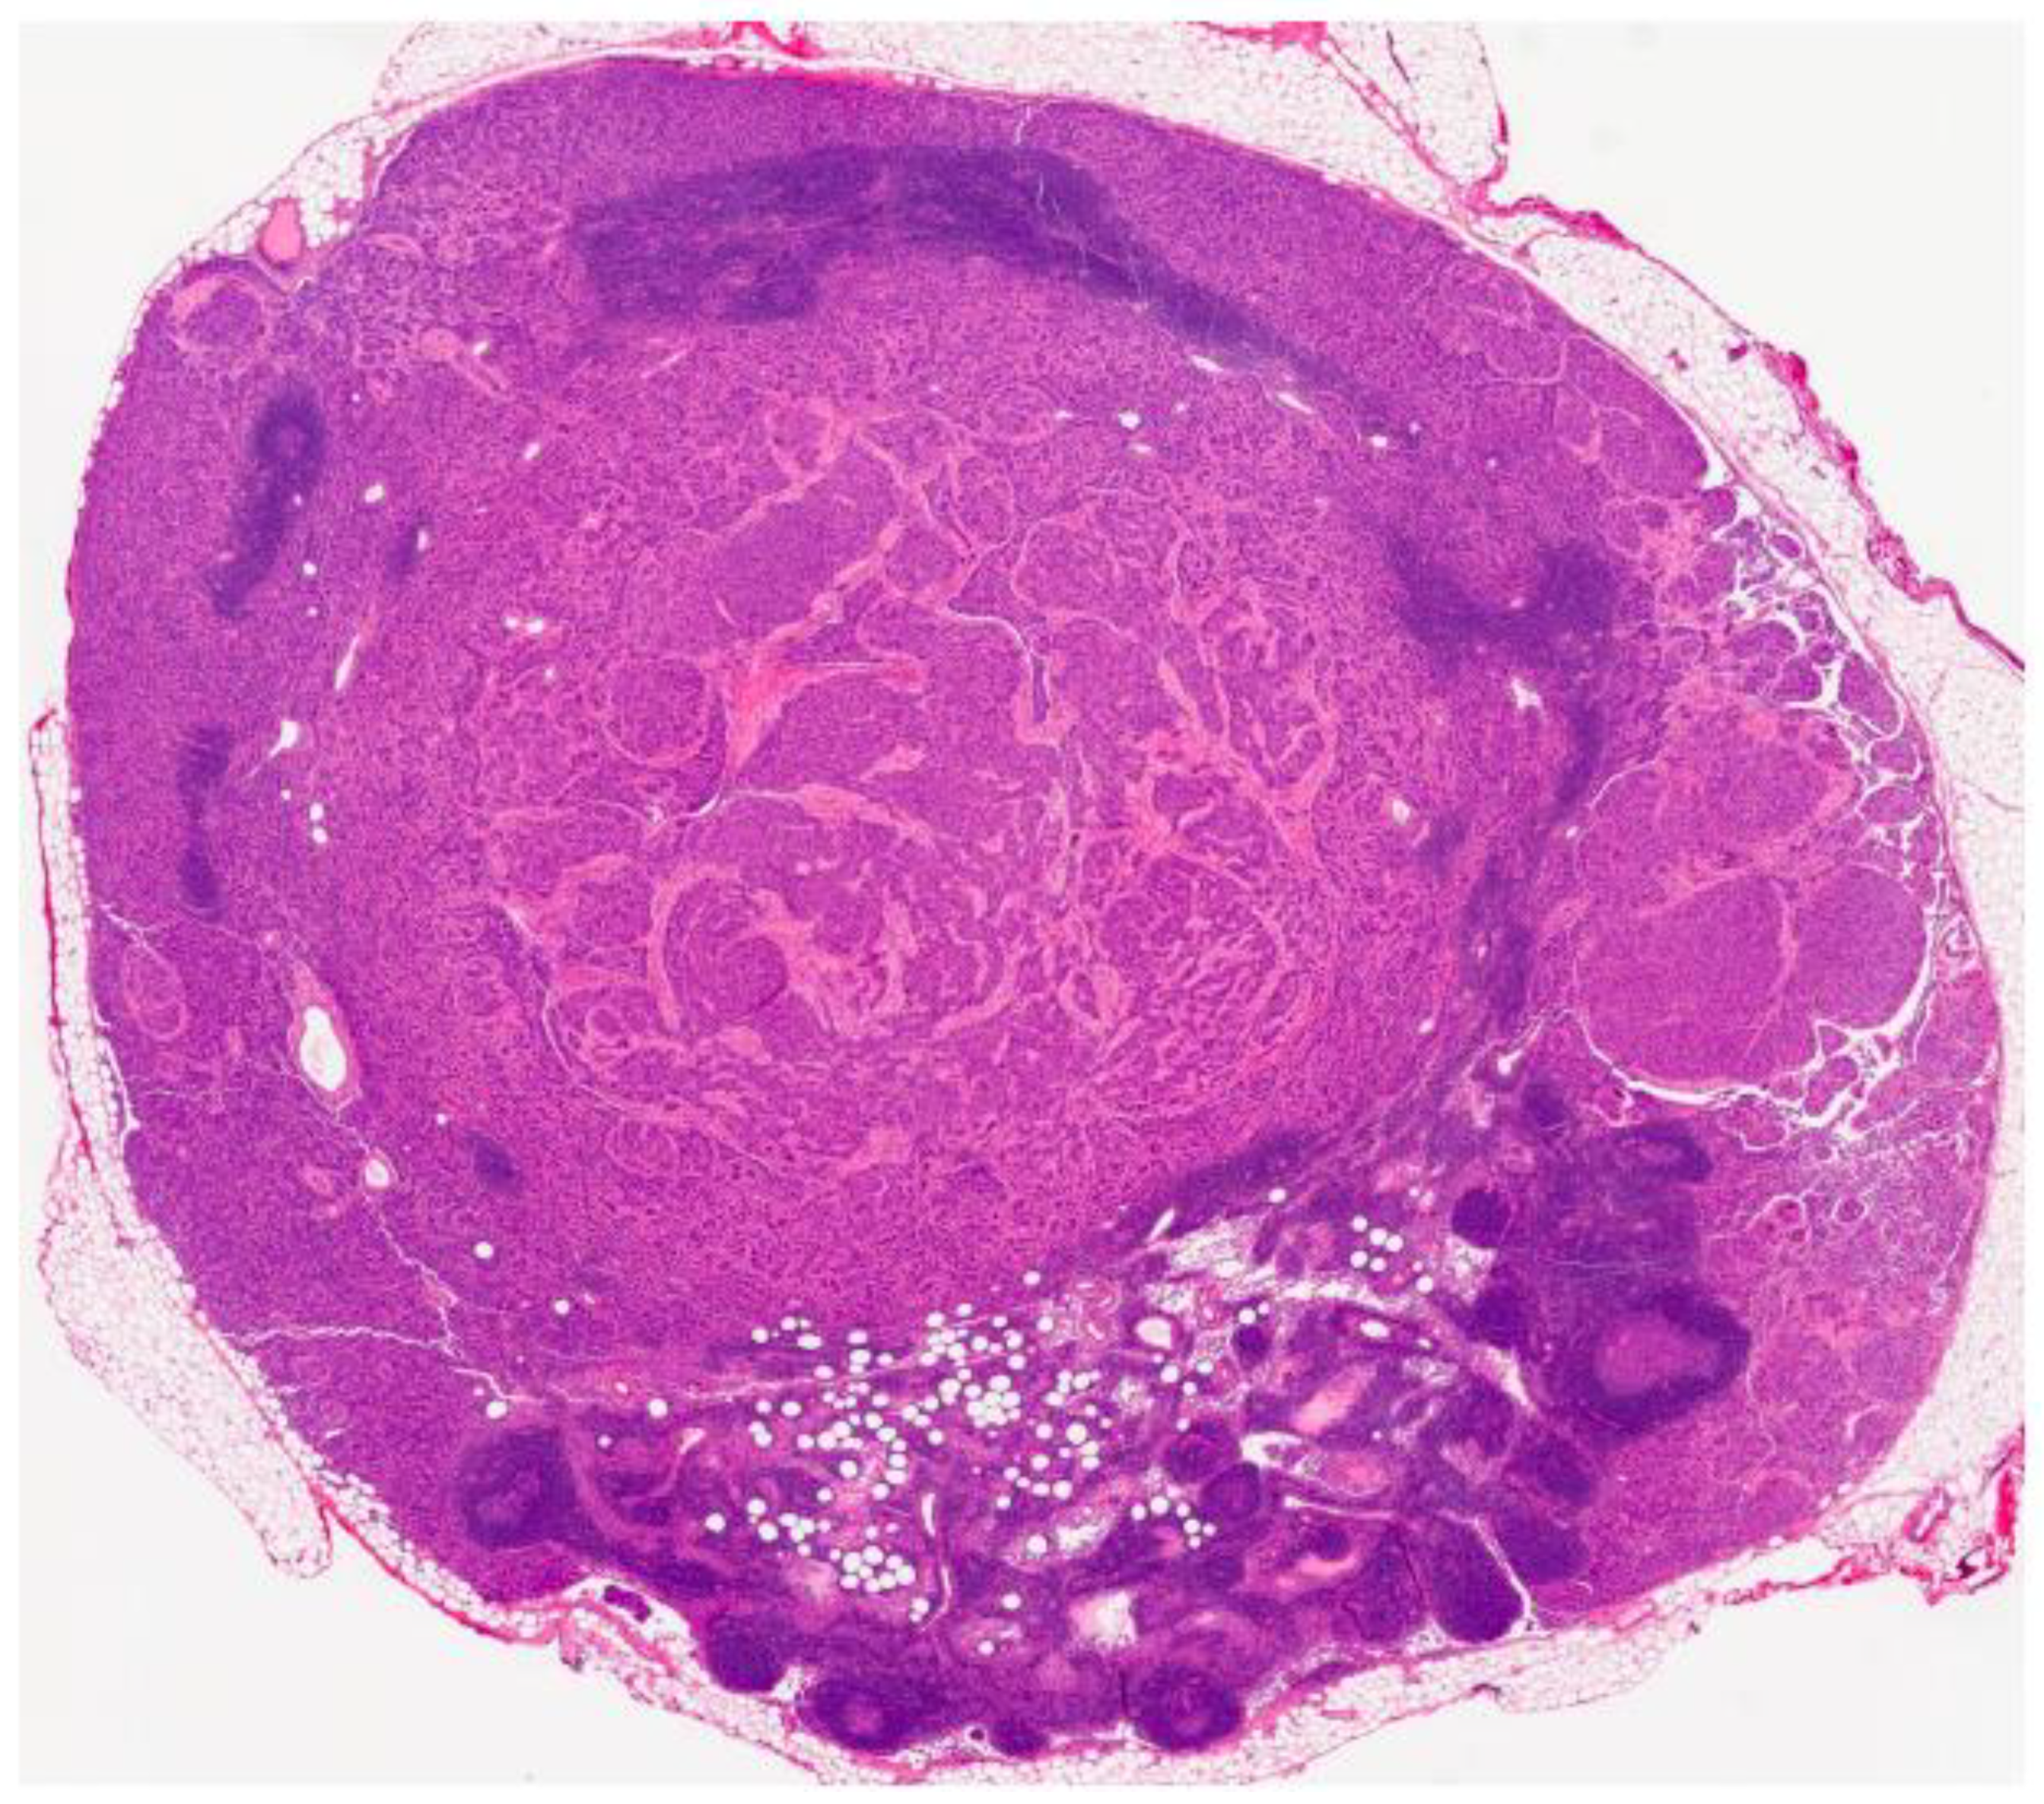

2. Case Presentation